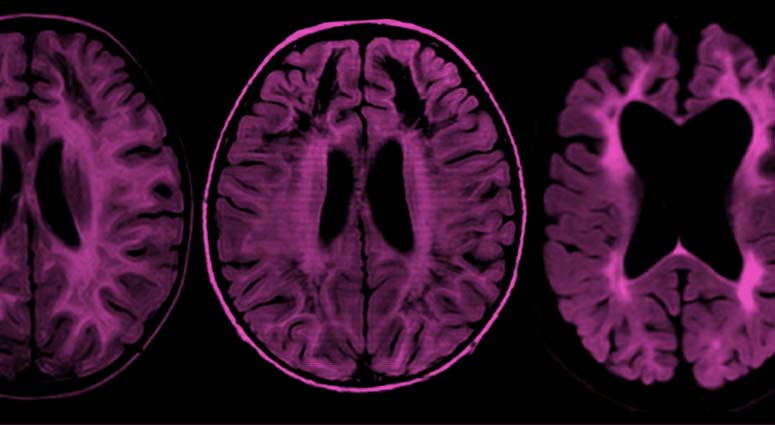

Le syndrome CACH est une maladie génétique de la famille des leucodystrophies hypomyélinisantes, qui présente une dégradation progressive de la substance blanche au niveau du cerveau. Il n’existe pas de traitement aujourd’hui, et seuls des soins symptomatiques sont offerts. Le nombre trop faible de patients connus, l’évolution imprévisible de la maladie, et l’absence de biomarqueur, compliquent la réalisation d’essais cliniques sur le syndrome CACH.